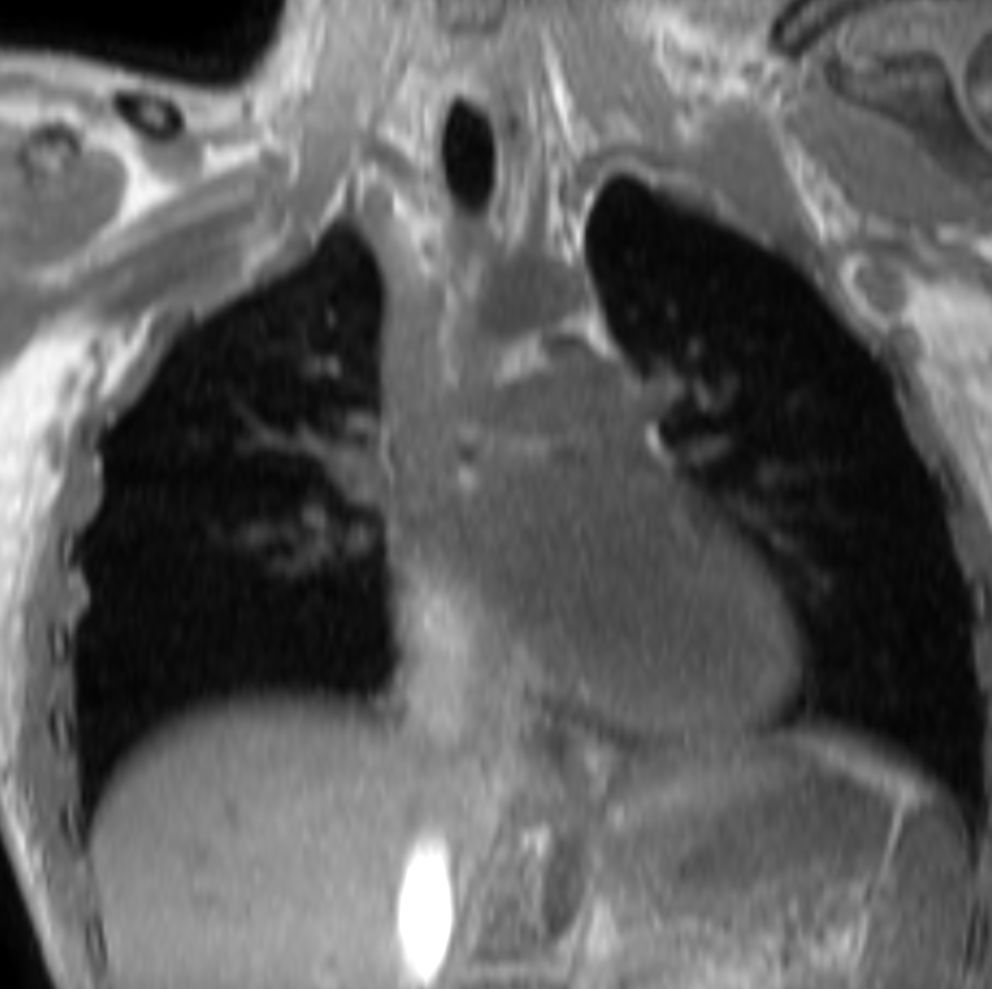

T1w mDIXON XD (In Phase)